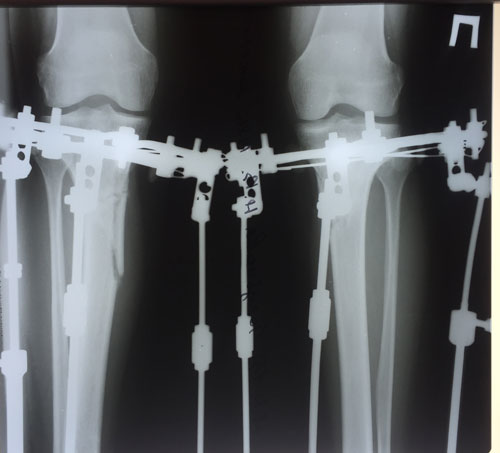

рентген в 90 дней.

Здравствуйте, Iskorka! По рентгену, сращение отличное, ждём на снятие аппаратов.